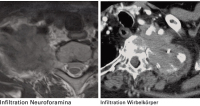

Infiltration - Wirbelsäule

Abbildung 4: In präoperativen MRT- und CT-Untersuchungen kann das genaue Ausmaß einer Infiltration der Wirbelsäule bestimmt werden.

Keywords: CTInfiltrationMRTWirbelsäule